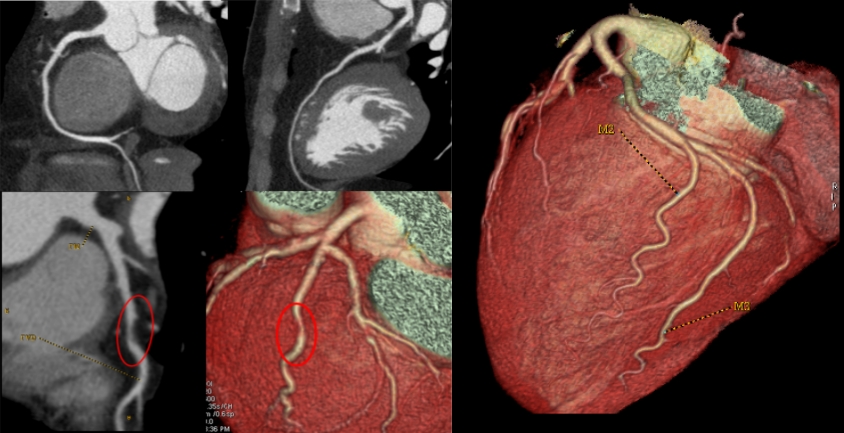

Früherkennung rettet Leben: Mit modernster Diagnostik schaffen wir im Sana Praevention München Schwabing die Grundlage für eine exakte Beurteilung Ihrer Gesundheit. Unser Schwerpunkt liegt auf hochauflösender Bildgebung wie Ganzkörper-MRT und Herz-CT, die auch kleinste Veränderungen sichtbar machen – lange bevor Symptome auftreten. So lassen sich Herz-Kreislauf-Erkrankungen, Tumoren oder andere Risiken frühzeitig erkennen und gezielt behandeln.

Dank der Kombination aus innovativer Medizintechnik, umfassender Laboranalytik und individueller ärztlicher Beratung erhalten Sie ein detailliertes Gesundheitsprofil. Dieses Wissen gibt Ihnen Klarheit und ermöglicht, gemeinsam mit unserem Team präzise Präventionsstrategien zu entwickeln.